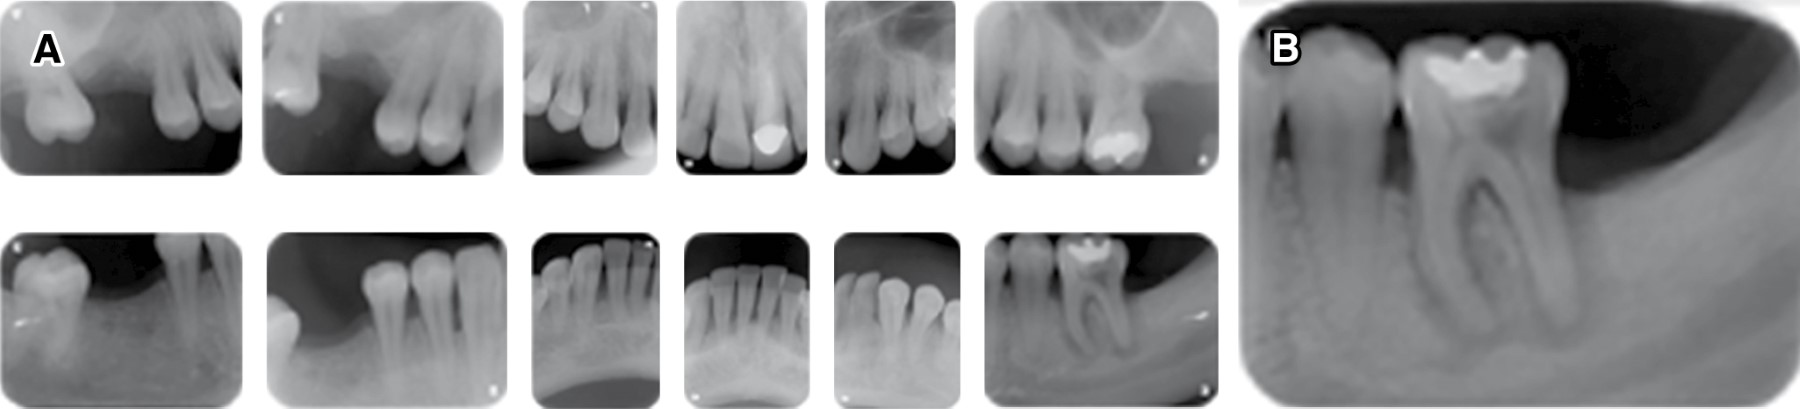

Figure 2